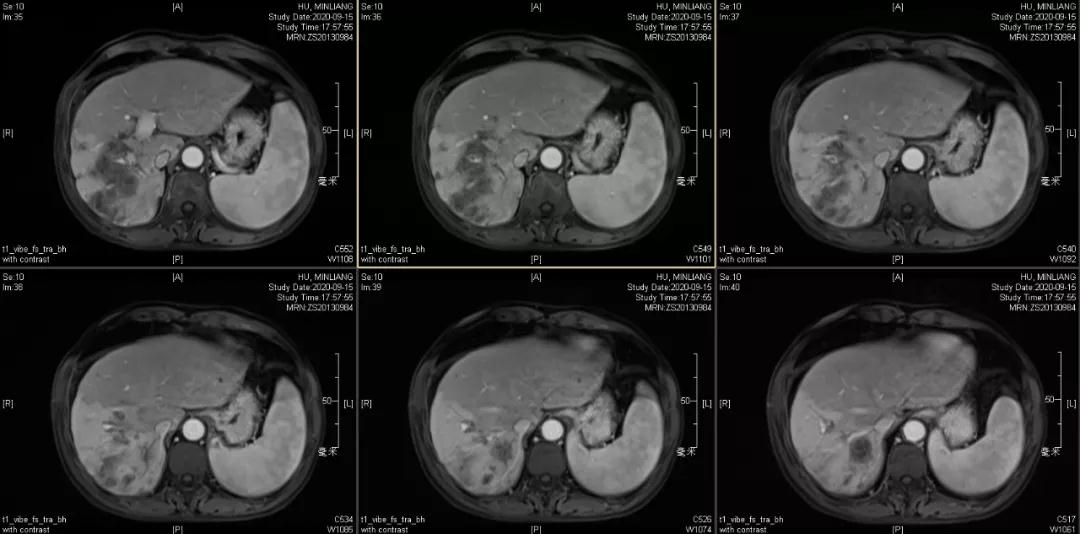

肝脏弹性超声:12kPa。腹部MRI平扫+增强:肝巨块结节性HCC(最大径18.4cm)伴肝内多发转移(最大径3.5cm),肝右静脉广泛癌栓形成;肝硬化伴门脉高压、脾大、少量腹水;肝囊肿;双肺多发转移。胸部CT平扫:两肺多发转移,两肺气肿伴肺大泡,两肺散在慢性炎症,右侧少量胸水。

Δ肝脏MRI,最大肿瘤18.4cm

肿瘤学评估(用药后2个月对比6个月):肝内主瘤明显缩小,动脉期强化降低;子灶消失;门脉右支癌栓明显缩小坏死;肺转移灶缩小,大部分消失。

2020-09-15

Δ治疗过程中病灶影像学变化